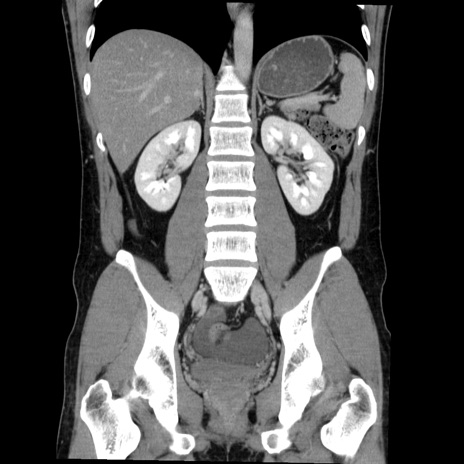

症例36(冠状断像)

【症例】20歳代 男性

【主訴】心窩部痛

【現病歴】今朝より上腹部痛あり。一旦軽快していたが再度出現したため救急要請。昨日夕に白身の魚を含む刺身を食べた。

【身体所見】BP 136/89mmHg、HR 74/min、BT 37.0℃、腹部:膨満、軟、心窩部に圧痛あり。反跳痛なし、筋性防御なし、腸雑音やや亢進あり。

【データ】WBC 17700、CRP 0.48